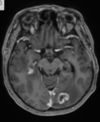

9

Q

A

Variante Creutzfeldt